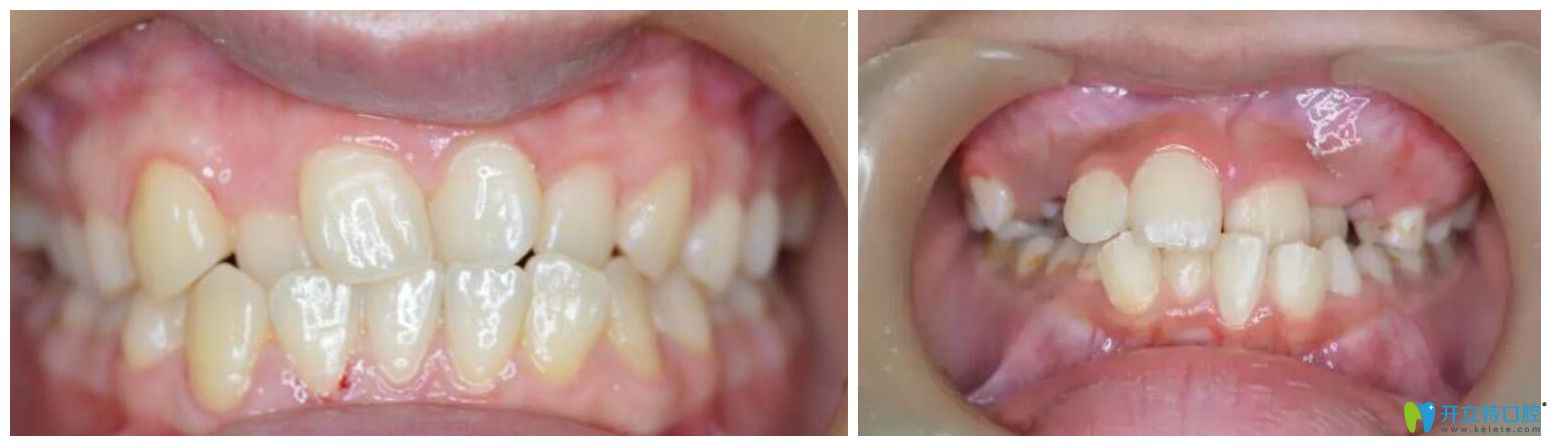

8、替牙期嚴(yán)重的牙齒擁擠

替牙期一般輕度擁擠可觀察,暫不處理;嚴(yán)重者,表現(xiàn)為個(gè)別或多個(gè)牙齒在各個(gè)方向的錯位;而且牙齒擁擠也妨礙局部牙齒的清潔而好發(fā)蛀牙、牙齦炎等。